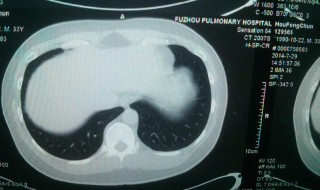

2、肺结节越来越常见,就是进行了胸部CT检查以后,会发现非常多的肺结节。肺结节引起的原因很多,有炎症感染、有良性肿瘤,也有恶心肿瘤。其中有一种结节就是磨玻璃样的,是指那些密度就是很淡薄向云雾样,像磨玻璃样这这一类的结节,它有一个特征就是它的密度。

3、就像我们看到的磨玻璃,它是半透明的,可以看到它下面的血管、气管等重要的结构,而实性的结节是看不到下面的结构的。因此这个结节专门是指这种密度的,结节有人叫磨玻璃也有人叫毛玻璃,因此它是一回事。